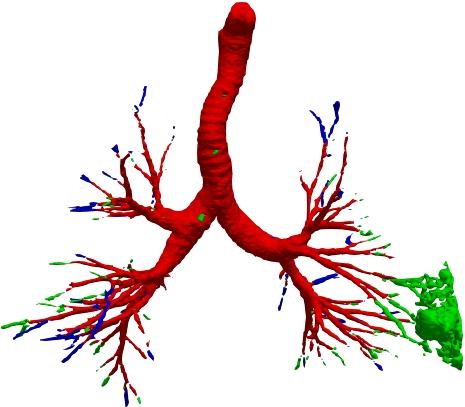

However, current state-of-the-art methods of lung organ segmentation still face several challenges and aspects for improvement. Firstly, the unlimited voxel values, multi-site imaging discrepancy and class imbalance in lung organ images can lead to false-negative and leakage issues in prior segmentation methods, which badly influences the critical early diagnosis of imperceptible lung diseases, e.g., lung fibrosis, nodule and hypertension, etc. Secondly, the presence of numerous slender branches, e.g., bronchioles and arterioles, which are easily lost during the recycled down/up-sampling procedure in Fig. 1, can result in discontinuity, detail loss, and coarse mask predictions. Thirdly, most CNN-based medical segmentation methods treat all points equally during the mask rendering stage, overlooking the vulnerability of border points in Fig. 1 (f) and the importance of explicit border modeling. Lastly, while Vision Transformer (ViT) has shown promise in computer vision tasks [1, 4], its quadratic operation complexity limits its application in 3D high-resolution CT images due to hardware constraints. Meanwhile, most specific datasets for medical image analysis are small and scarce due to laborious manual annotation and privacy protection, which badly restricts the potential of transformer-based top-tier methods.

We qualitatively analyze our method on four challenging lung organ datasets. In Fig. 5, SFCN [19] suffers from severe false positives and some false negatives, especially for the big green areas of airway leakages. WNet [22] is mainly influenced by false negatives on the main trachea. For the Fibrosis dataset at the third row, it also encounters the false negative problem in the terminal bronchioles moderately. FANN [10] bears the slight discontinuity issue of false negative in the terminal bronchioles of BAS dataset, and the severe discontinuity and airway leakage problems on the more challenging Fibrosis benchmark. Instead, due to the above two novel modules, our method can solve the defects of false negative, discontinuity, and leakages faced by past advanced methods. Besides, the results on PARSE22 artery dataset in supplementary Fig. 6 also proves this.